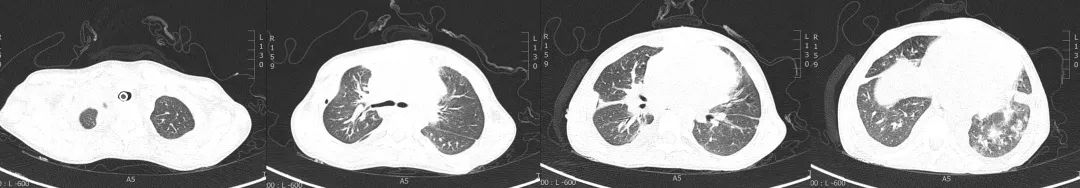

客观资料: 肺部体查(视诊:开胸术后、气管切开术后改变;触诊:双侧呼吸动度对称;叩诊:清音;听诊:双肺呼吸音清,未闻及干湿性啰音),氧疗参数(模式:HFNC;氧流量:30L/min;FiO2:25%;温度:34℃),生命体征(T:36.3℃;P:120次/分;R:18次/分;BP:92/57mmHg),实验室检查(WBC:5.39×10^9/L;N%:83.2%;L%:9.8%;HGB:97g/L;PLT:213×10^9/L;CRP:6.95mg/l;PCT:0.25ng/ml;TnI:<0.05ng/ml;BNP:490pg/ml;Mb:119μg/l;CKMB:16.1u/l;D-二聚体:>5000μg/ml;ALT:20.3u/l;AST:26.6u/l;ALB:41.4g/l;BUN:3.82mmol/l;Cr:23.9μmol/l),血气分析(PH:7.405;PCO2:39.6mmHg;PO2:96.8mmHg;HCO3-:25mmol/l;SaO2:97.2%;FiO2:25%;P/F:387.2mmHg)。辅助检查(2019年6月10日CT:双肺弥漫性渗出灶较前明显减少,双侧斜裂积液及心包腔内积液稍减少;下肢血管彩超:双下肢深静脉血流通畅)。

经过临床-康复-护理积极地综合治疗与管理,影像学对比发现:各叶段支气管通畅,双侧胸腔积液及心包腔积液较前减少。

图:2019年6月10日CT

图:2019年7月24日CT